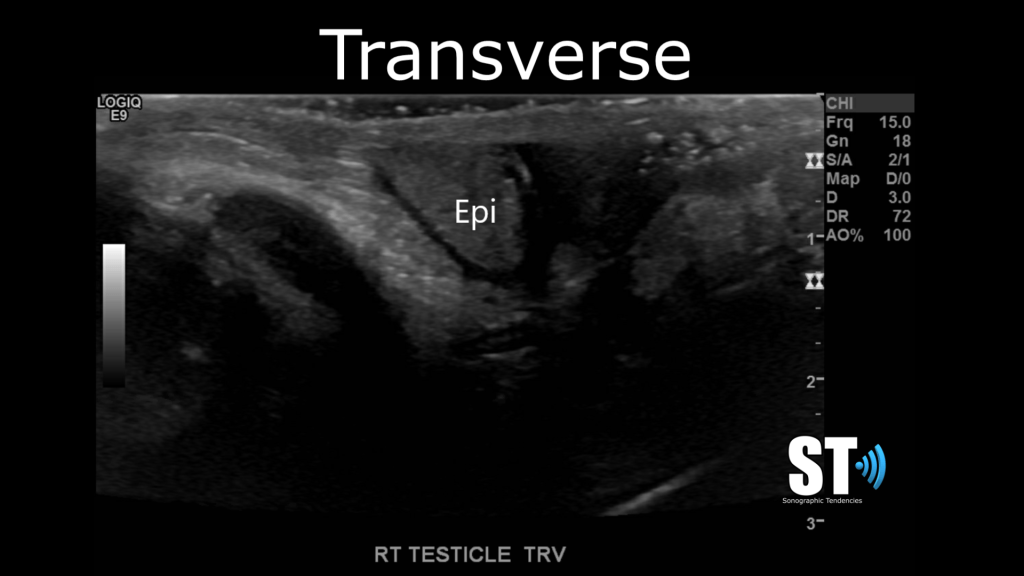

Transverse

In transvers beginning at the superior pole take images of starting at the epididymal head and capture images of the superior, mid section and inferior poles of the testis.